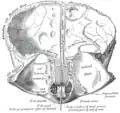

Левая теменная кость. В верхней части видны грануляции